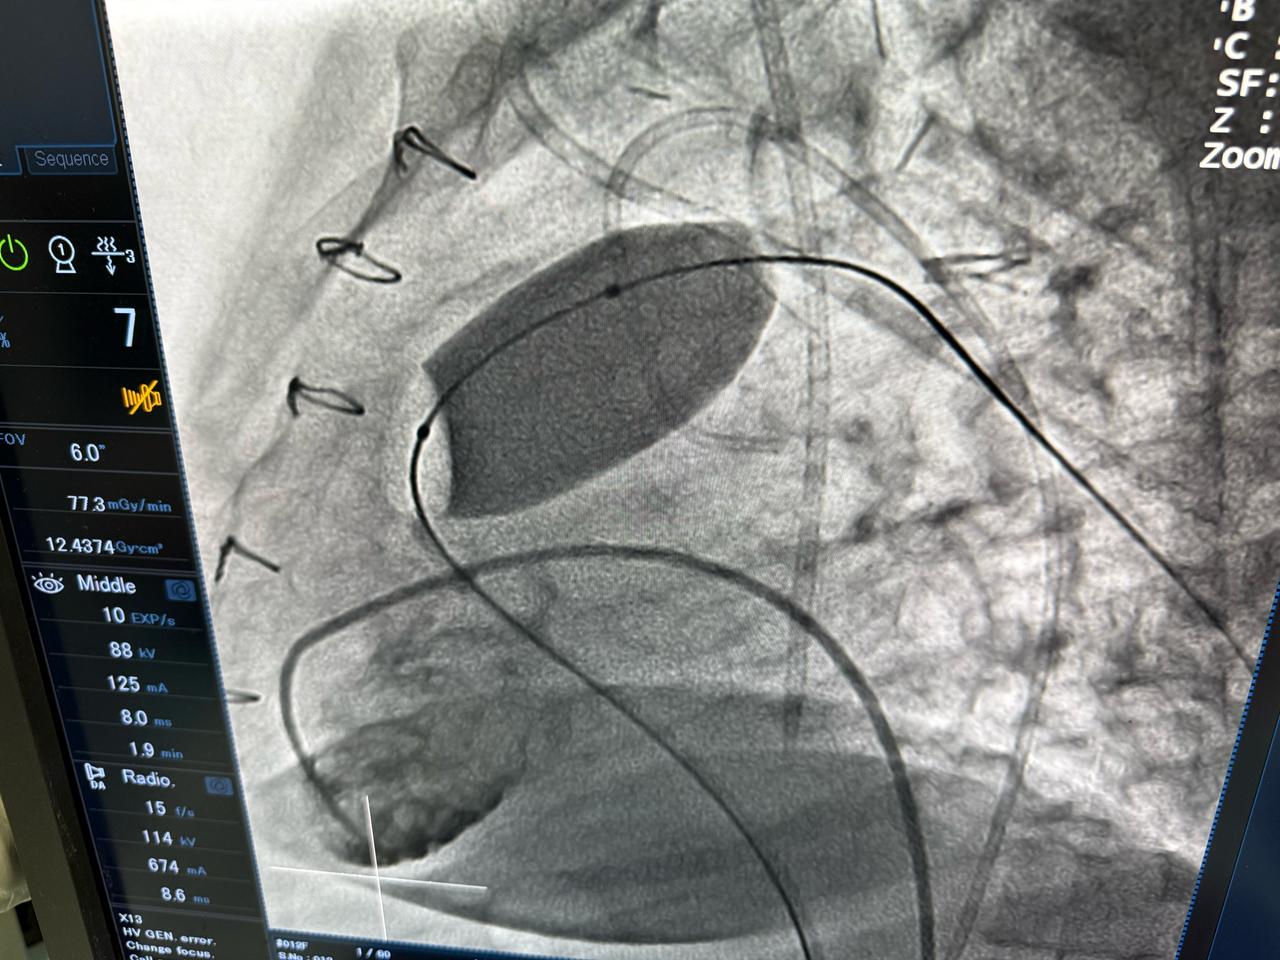

أعلنت وزارة الصحة والسكان، عن نجاح عملية دقيقة لتغيير الصمام الرئوي بالقسطرة لشابة تبلغ من العمر 23 عامًا، كانت تعاني من ارتجاع شديد بالصمام الرئوي نتيجة جراحة رباعي فالوت السابقة، وهو أحد أكثر العيوب الخلقية القلبية تعقيدًا.

وصرّح الدكتور حسام عبد الغفار، المتحدث الرسمي لوزارة الصحة والسكان، بأن العملية أُجريت باستخدام أحدث التقنيات العالمية داخل أكاديمية قلب المبرة، التابعة للمؤسسة العلاجية، على يد نخبة من الخبراء المصريين، مؤكدًا أن هذا الإجراء الطبي المتقدم، الذي تجاوزت تكلفته مليون جنيه، يعكس قدرة الفرق الطبية المصرية على تنفيذ أدق التدخلات القلبية وفق أعلى المعايير الدولية.

وجرت العملية تحت إشراف الدكتور محمد إبراهيم شقوير، رئيس المؤسسة العلاجية، والدكتور هشام الفخراني، مدير مستشفى مبرة مصر القديمة، وبقيادة فريق طبي متخصص برئاسة الدكتور محمد صبري، رئيس قسم القلب، والدكتور أحمد السواح، مدير وحدة القسطرة، والدكتور علي جلال، مدير وحدة الأمراض الخلقية.